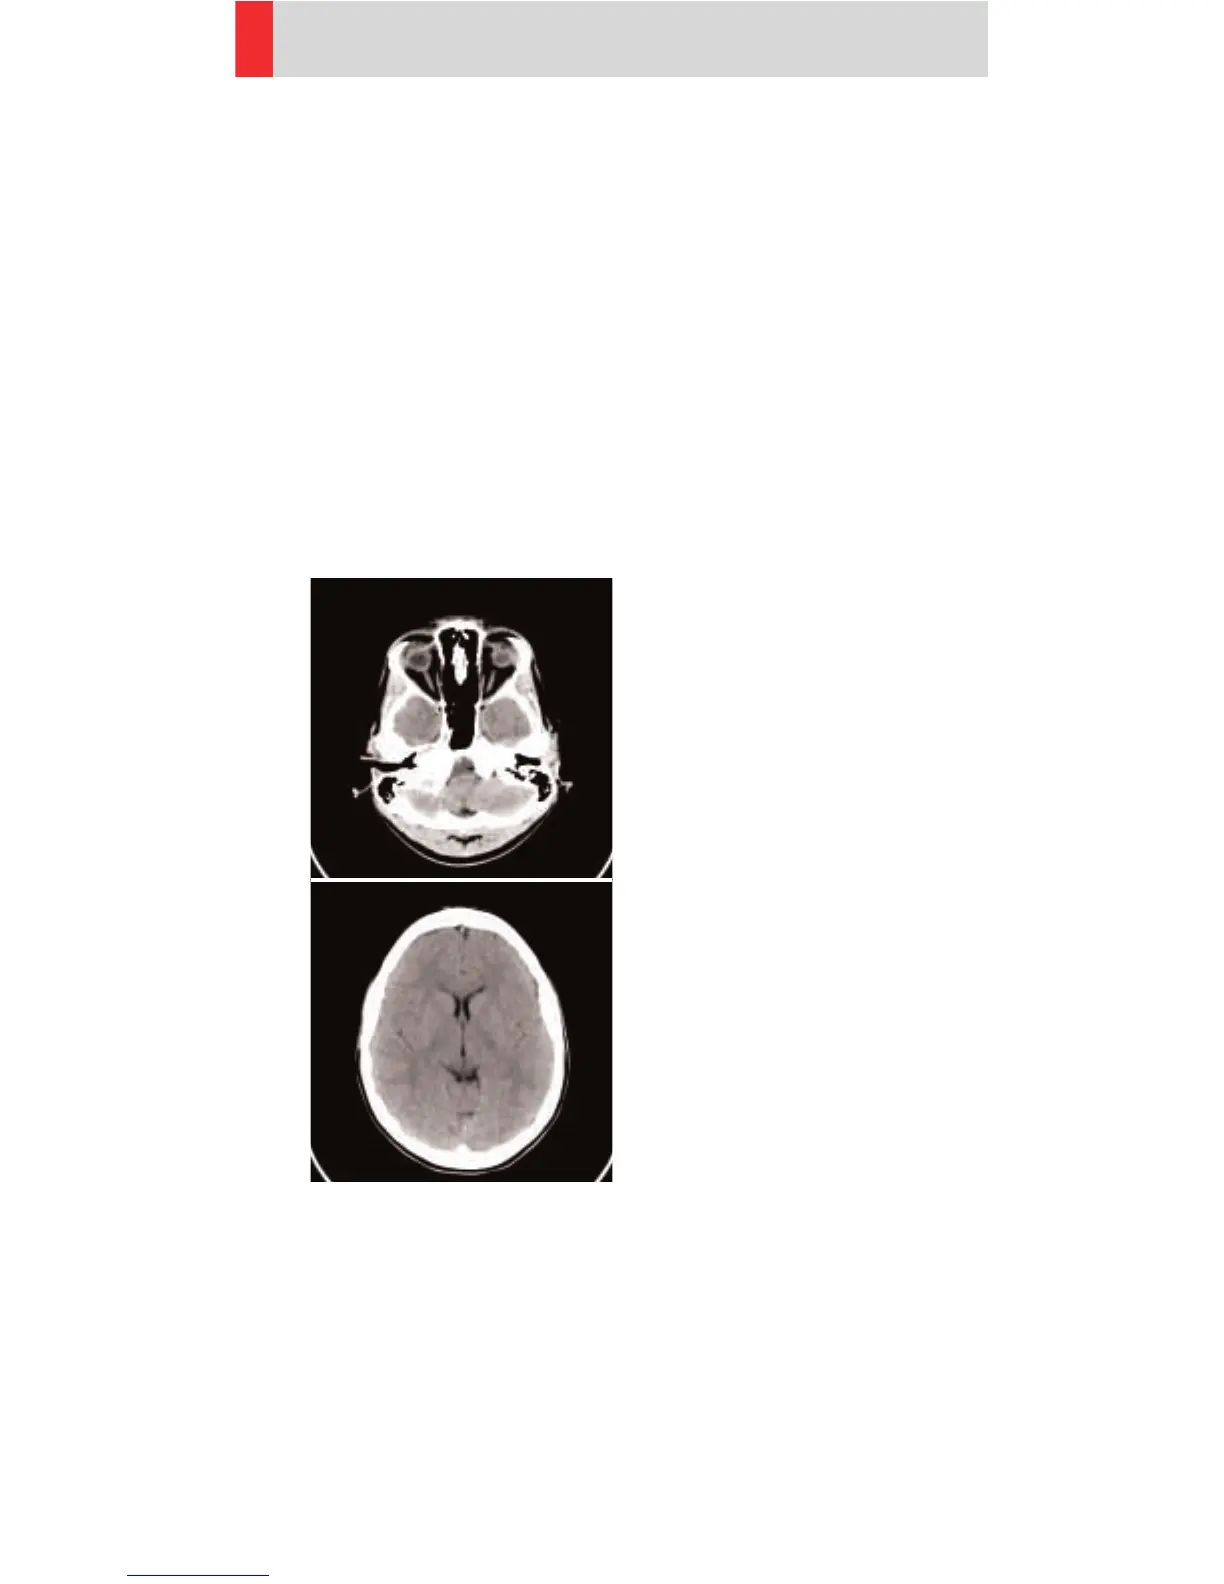

HeadSeq

Indications:

Sequence mode for routine head studies, e. g.

stroke, brain tumors, cranial trauma, cerebral atrophy,

hydrocephalus, and inflammation, etc.

Two ranges are predefined. One for the base of the

skull and one for the cerebrum, the scan length for the

entire head is 125 mm.

For both ranges a typical gantry tilt of -20° is predefined.